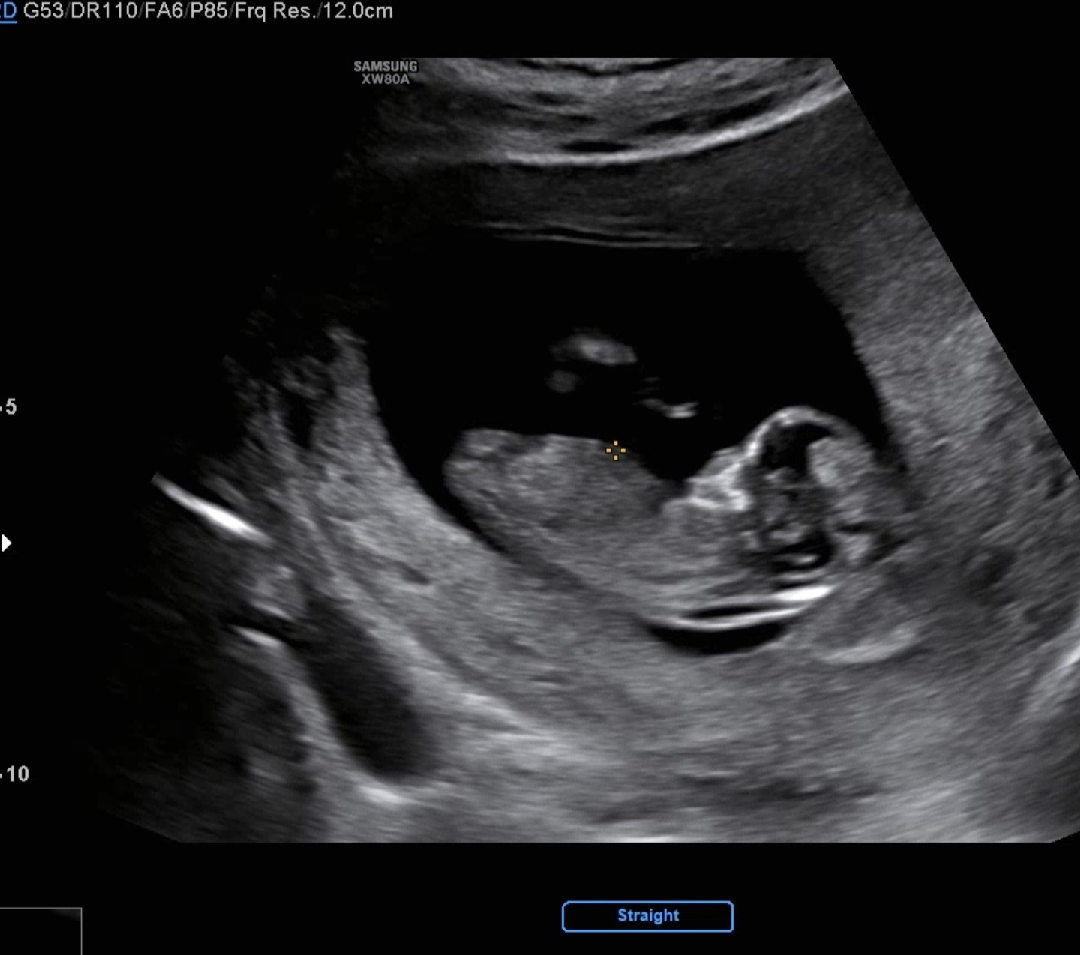

12주1일 각도법 한번만 봐주세요